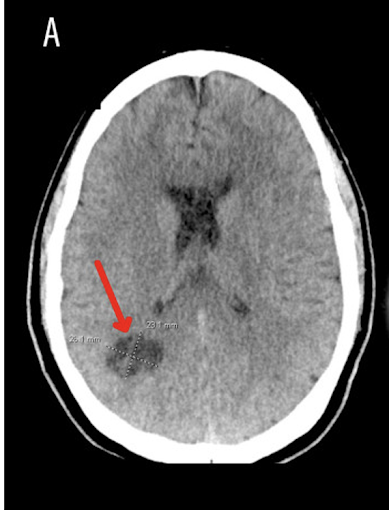

Zum Zeitpunkt der Erstvorstellung im Krankenhaus zeigten die Vitalwerte des Patienten keine Auffälligkeiten – so auch die neurologische Untersuchung. Aufgrund der besorgniserregenden und anhaltenden Veränderung der Migräneanfälle des Patienten wurde zunächst eine CT-Untersuchung durchgeführt und im Anschluss ein MRT des Gehirns. Die Bildgebung ergab folgende Befunde:1

Bildabschnitt A: Im CT des Kopfes zeigte sich eine Anhäufung neben dem Okzipitalhorn des rechten Seitenventrikels. Diese betrug maximal 2,6 × 2,3 cm (roter Pfeil).1